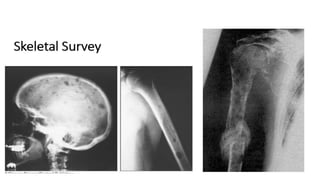

• PAIN

• Back or chest bone pain as result of vertebral or rib fractures at sites of

osteopenia or from lytic bone lesions is present at the time of diagnosis in

approximately 60 percent of patients.247 The pain is usually worse with

movement and at night. Pathologic fractures of long bones can ensue as well.